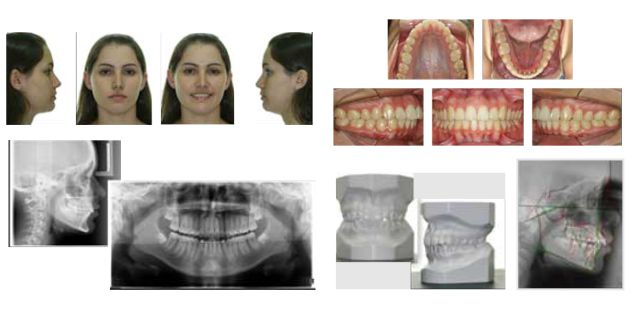

Fotografias Extrabucais e Intrabucais

Modelos de Estudo

Documentações Digitais